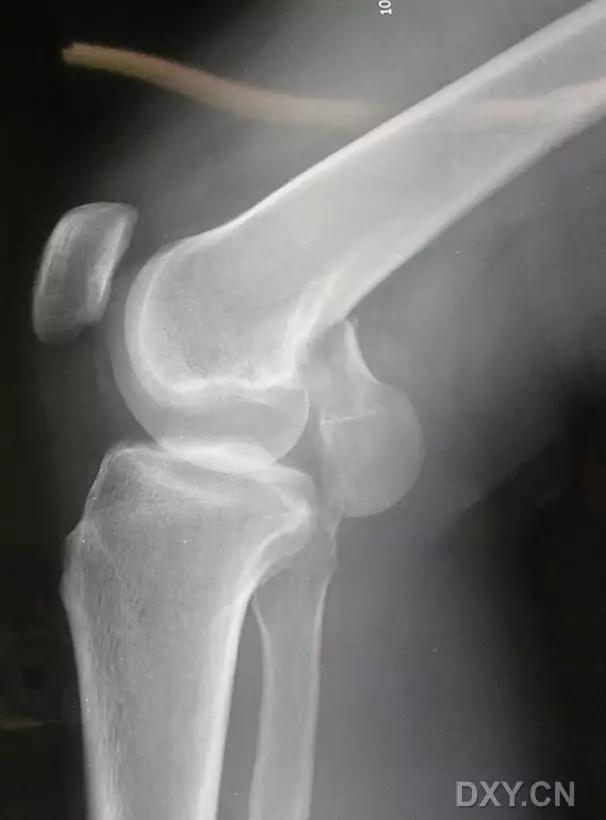

5. Hoffa 骨折

指股骨远端冠状面的骨折。

病例 1:一般股骨髁间、髁上粉碎骨折中含 Hoffa 骨折的不少见,但单纯后髁骨折则很少见。

侧位片